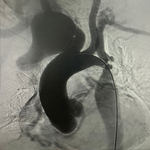

Imagen Instalaron en Concepción los dos primeros stents biodegradables

27-02-2024

Instalaron en Concepción los dos primeros stents biodegradables

para tratar estenosis biliar benigna en Chile